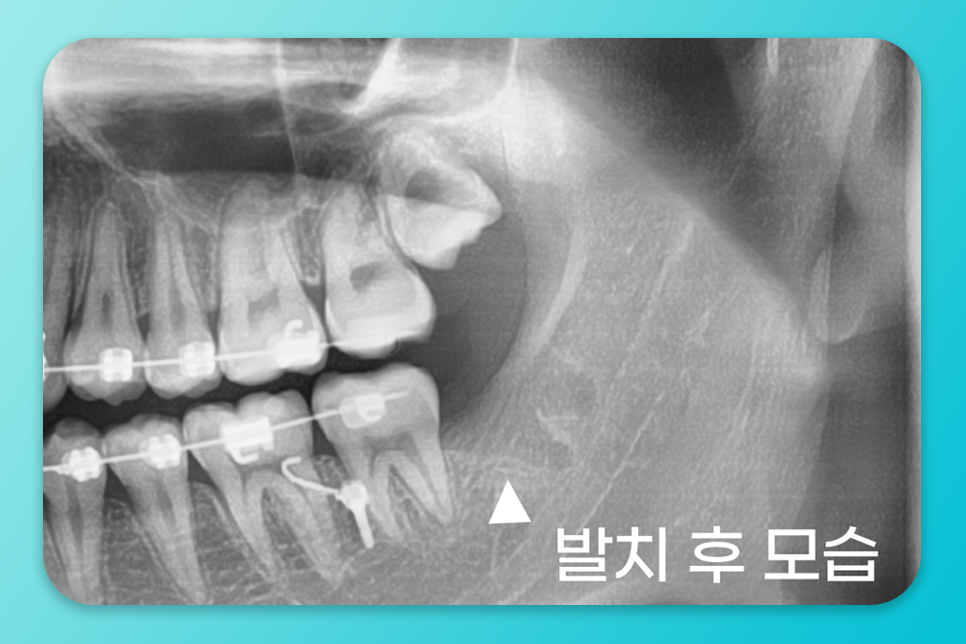

발치는 이렇게 진행됩니다.

급성 부종이나 통증이 심하면

약물로 진정시킨 뒤

발치 약속을 잡아 드립니다.

약속일에 방문하시면

국소마취를 충분히 진행하고

발치를 하는데

난이도가 높거나 매복이 깊으면

절개, 봉합이 함께 들어갈 수 있어요.

이후에는 처방약 복용, 얼음찜질(초기),

구강 위생 관리를 하면서

경과를 보게 됩니다.

개인차는 있지만 대부분 며칠에서 1주 내

일상 복귀가 가능하고

실밥 제거가 필요하면

방문 날짜에 맞춰 깔끔히 마무리돼요.